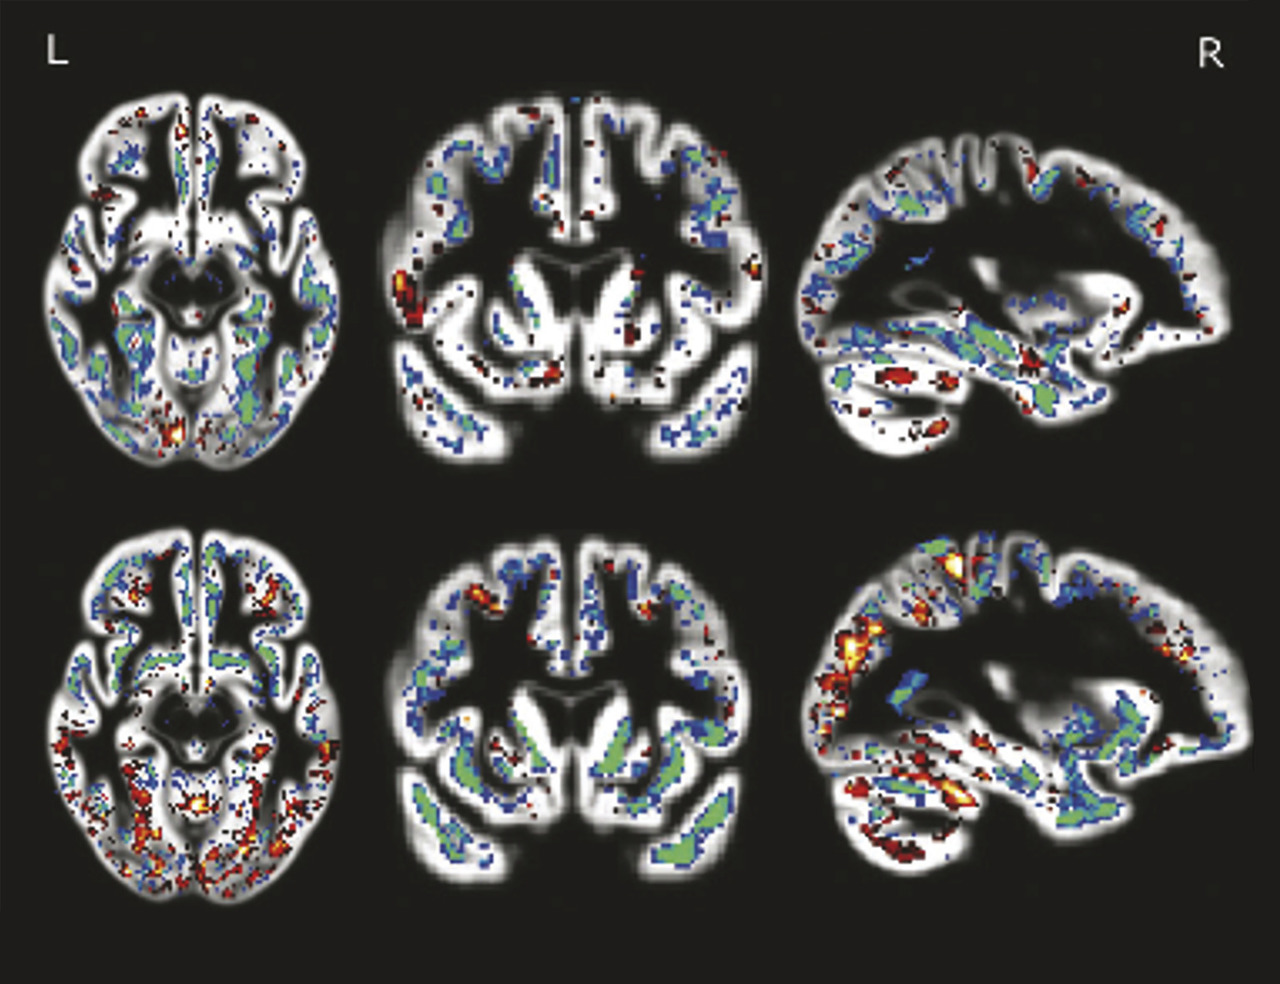

Pour visualiser le cerveau d’un patient atteint de maladie d’Alzheimer, le recours aux imageries par résonance magnétique (IRM) de haute performance semble clairement la meilleure attitude (fig. 1 à 4 ). Toutefois, l’élimination de nombreuses causes de démence peut être obtenue par une bonne anamnèse clinique. Cependant, de nombreuses études montrent qu’une bonne anamnèse un bilan neuropsychologique classique associés à des tests sanguins de routine sont insuffisants pour faire un diagnostic précis d’un patient atteint de démence.1 Ainsi, chaque patient ayant un bilan diagnostique standard devrait aussi avoir une IRM ou une tomodensitométrie pour exclure les rares méningiomes ou anévrismes massifs à croissance lente, les accidents vasculaires cérébraux silencieux et/ou les maladies vasculaires diffuses, car ils sont tous potentiellement traitables.

L’IRM fournit-elle un biomarqueur anatomique non invasif précis pour diagnostiquer les individus sans les hospitaliser ? L’analyse visuelle ne peut certainement pas le faire ; aucun radiologue, même expérimenté, ne diagnostique la maladie d’Alzheimer à partir d’une IRM clinique. De nombreuses études comparant les cohortes de patients et de témoins par IRM (structurelles et fonctionnelles) montraient différents profils d’atrophie cérébrale associés à des démences dégénératives.4 Jusqu’à présent, les analyses d’images d’individus n’ont pas été suffisamment sensibles pour identifier ces profils d’atrophie. De nombreux progrès dans la collecte des IRM sensibles aux différentes caractéristiques de tissus cérébraux sont en cours de développement ; il faut donc espérer qu’une association de profils IRM permettra une telle identification individuelle dans l’avenir.

Les avancées majeures récentes en informatique, notamment en gestion et analyse de données, offrent une autre vision pour l’avenir. L’apprentissage automatique permet aux ordinateurs d’analyser des images IRM structurelles standard afin de distinguer avec précision les personnes montrant un profil d’atrophie spécifique, un motif caractéristique de la maladie d’Alzheimer validé par l’autopsie.5 La possibilité de classer les individus par IRM change radicalement la donne ! Ces images d’IRM représentent ainsi des biomarqueurs anatomiques spécifiques à la maladie d’Alzheimer.

Une étude a examiné un groupe de patients atteints de maladie d’Alzheimer et un groupe de volontaires sains, les deux appartenant à la cohorte clinique ADNI, disponible en ligne pour la recherche. Seulement 15 des 20 patients ayant une maladie d’Alzheimer diagnostiquée cliniquement avaient le motif IRM typique de la maladie d’Alzheimer, de sorte que 5 n’avaient pas une démence due à la maladie d’Alzheimer. Trois IRM de 20 volontaires normaux montraient le motif d’atrophie typique de la maladie d’Alzheimer, suggérant qu’il s’agissait de sujets atteints de la maladie d’Alzheimer compensée. Une autre étude épidémiologique montre que le motif d’atrophie spécifique de la maladie d’Alzheimer a une valeur pronostique par rapport à l’apparition de symptômes de la démence. À terme, il pourrait être possible d’évaluer les effets des traitements associés aux motifs types d’atrophie cérébrale par des essais cliniques fondés sur des cohortes beaucoup plus homogènes et petits. Des tentatives de corrélations des marqueurs génétiques, biochimiques et anatomiques (IRM) ensemble sont en cours d’exploration pour affiner un diagnostic encore plus précis et plus précoce.